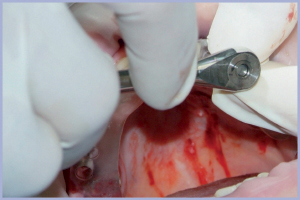

Dopo aver ultimato il fresaggio del sito, rimuovo le boccole per permettere l’inserimento guidato degli impianti. Per fare questo, sostituisco i carrier presenti nelle confezioni degli impianti con i carrier per chirurgia guidata; avvito quindi l’impianto nel foro corrispondente presente sul blocchetto cambio carrier, rimuovo il carrier dall’impianto e ci inserisco il nuovo carrier che fa presa con l’impianto tramite il gommino presente sul tratto di connessione interna. Porto a dimora l’impianto attraverso il foro, lasciato dalla rimozione della boccola, nella guida; il diametro del carrier é uguale al diametro della boccola. L’inserimento dell’impianto avviene tramite gli strumenti tradizionali (manipolo con raccordo o cricchetto) fino ad arrestarsi quando la tacca di riferimento arriva al margine superiore della guida (Figg. 31-50).

- Fig. 45 – Proseguimento dell’inserimento guidato dell’impianto con il cricchetto